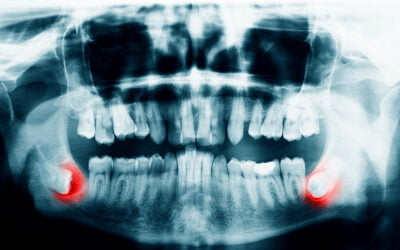

Benefits of Dental X-rays

Taking oral x-rays helps our Yuba City dentist see inside your mouth, jaws and teeth to diagnose problems, prevent disease and assess bone health. Annually our dental professionals plan to take x-rays of our patients as part of a regular exam and cleaning. This helps...